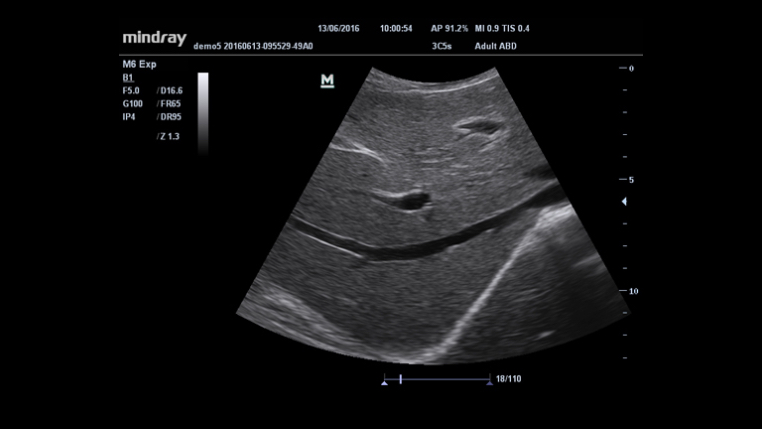

O M6 é um sistema de ultrassom portátil, projetado para oferecer precisão, versatilidade e mobilidade, permitindo diagnósticos confiáveis à beira do leito. Com um design leve e ergonômico, proporciona alta qualidade de imagem e eficiência operacional em ambientes hospitalares e clínicos.

O M6 da Mindray é um ultrassom portátil que combina tecnologia de imagem avançada e recursos otimizados, garantindo resultados diagnósticos superiores.

- Convexos: 3C5s, C11-3s.